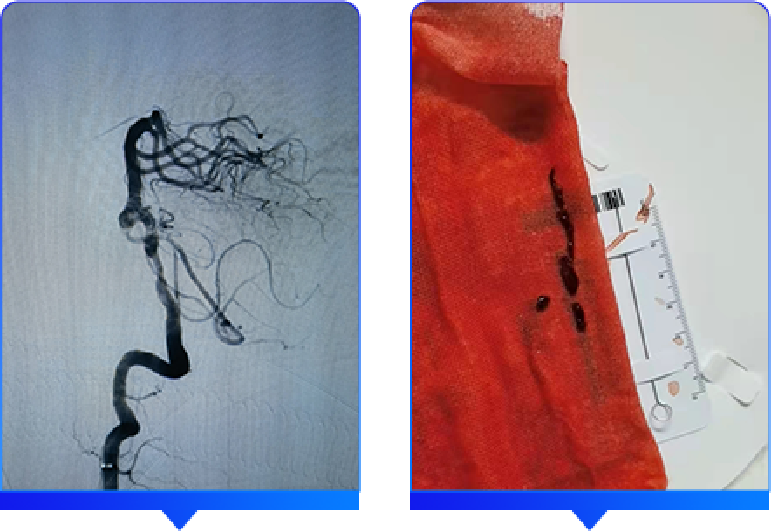

术后穿刺点管理

采用StarClose SE 血管闭合器对股动脉穿刺点进行闭合管理。

整个手术过程很成功,但需要强调的是不能忽视股动脉穿刺点的管理,否则可能会引起血管穿刺点相关并发症的发生,例如:血肿,腹膜后出血,假性动脉瘤等,对患者带来不良愈后。

此次对于股动脉穿刺点闭合采用的是StarClose SE 血管闭合器,原理是采用钛夹血管外夹闭的方式对股动脉穿刺点进行闭合,一期闭合,手术台上即可确定止血效果,其主要优势: 即刻止血,操作简便,在血管内不留任何痕迹,不影响二次穿刺;给临床带来的益处是医生更加放心下手术台,缩短了整体手术时间,减少了导管室工作人员的压力,并发症少减轻了医护人员的护理难度和工作量;对患者而言术后制动时间缩短,减少了血栓的风险,炎症反应小,同时减少需要服用止疼药或插导尿管等的时间,可以提早出院,患者体验好;对科室而言,可提高床位周转率,减少患者住院费用。重视穿刺点的管理操作,有时候给临床带来的获益良多!